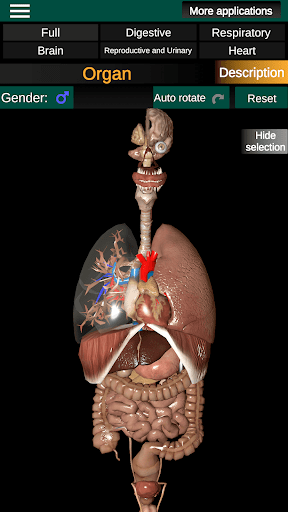

Menampilkan model anatomi 3D dari organ utama tubuh manusia dan penjelasannya masing-masing.

Apa yang ada di aplikasi?

* Sistem pencernaan, termasuk lambung, usus kecil, usus besar, dan animasi sistem ini.

* Sistem pernafasan, yang meliputi trakea, bronkus, paru-paru dan animasi sistem ini.

* Sistem reproduksi, yang meliputi organ reproduksi pria dan wanita.

* Otak, yang meliputi otak, otak kecil, dan batang otak.

* Jantung, yang meliputi atrium, ventrikel, aorta, dan animasi organ ini.

* Mudah diakses dan dinavigasi (zoom, rotasi 3D).

* Sembunyikan atau tampilkan informasi.

* Bandingkan organ pria dan wanita.

* Deskripsi masing-masing organ.